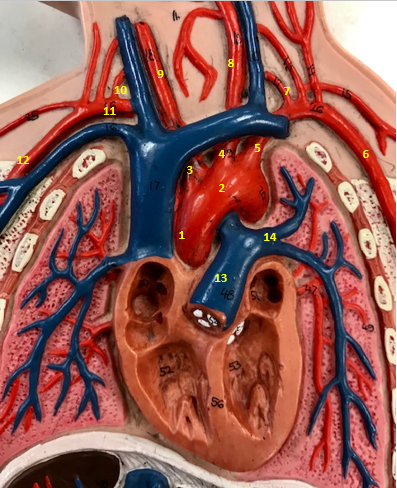

Aorta

Name #2

Brings blood out of left ventricle

Function of aorta

Brachiocephalic artery

Name #3

Supplies oxygenated blood to right arm shoulder neck and head

Function of brachiocephalic artery

Left common carotid artery

Name #4

Supplies oxygenated blood to left neck and head

Function of left common carotid artery

Left subclavian artery

Name #5

Supplies oxygenated blood to left arm shoulder

Function of left subclavian artery

Left axillery artery

Name #6

supplies blood to left armpit and upper limb

Function left axillary artery (6)

Left vertebral artery

Name #7

Supplies blood to brain and spinal cord

Function of left vertebral artery (7)

Left common carotid artery

Name #8

Supplies blood to left neck and head

Function of left common carotid artery (8)

Right common carotid artery

Name #9

Supplies oxygenated blood to right neck and head

Function of right common carotid artery (9)

Right vertebral artery

Name #10

Supplies blood to brain and spinal cord

Function of right vertebral artery (10)

Right subclavian artery

Name #11

Supplies blood to right arm and shoulder

Function of right subclavian artery

Right axillery artery

Name #12

Supplies blood to right armpit and upper limb

Function of right axillery artery (12)

Pulmonary trunk

Name #13

Bring blood out of right ventricle to lungs

Function of pulmonary trunk (13)

Left pulmonary artery

Name #14

Bring blood to left lung

Function of left pulmonary artery (14)